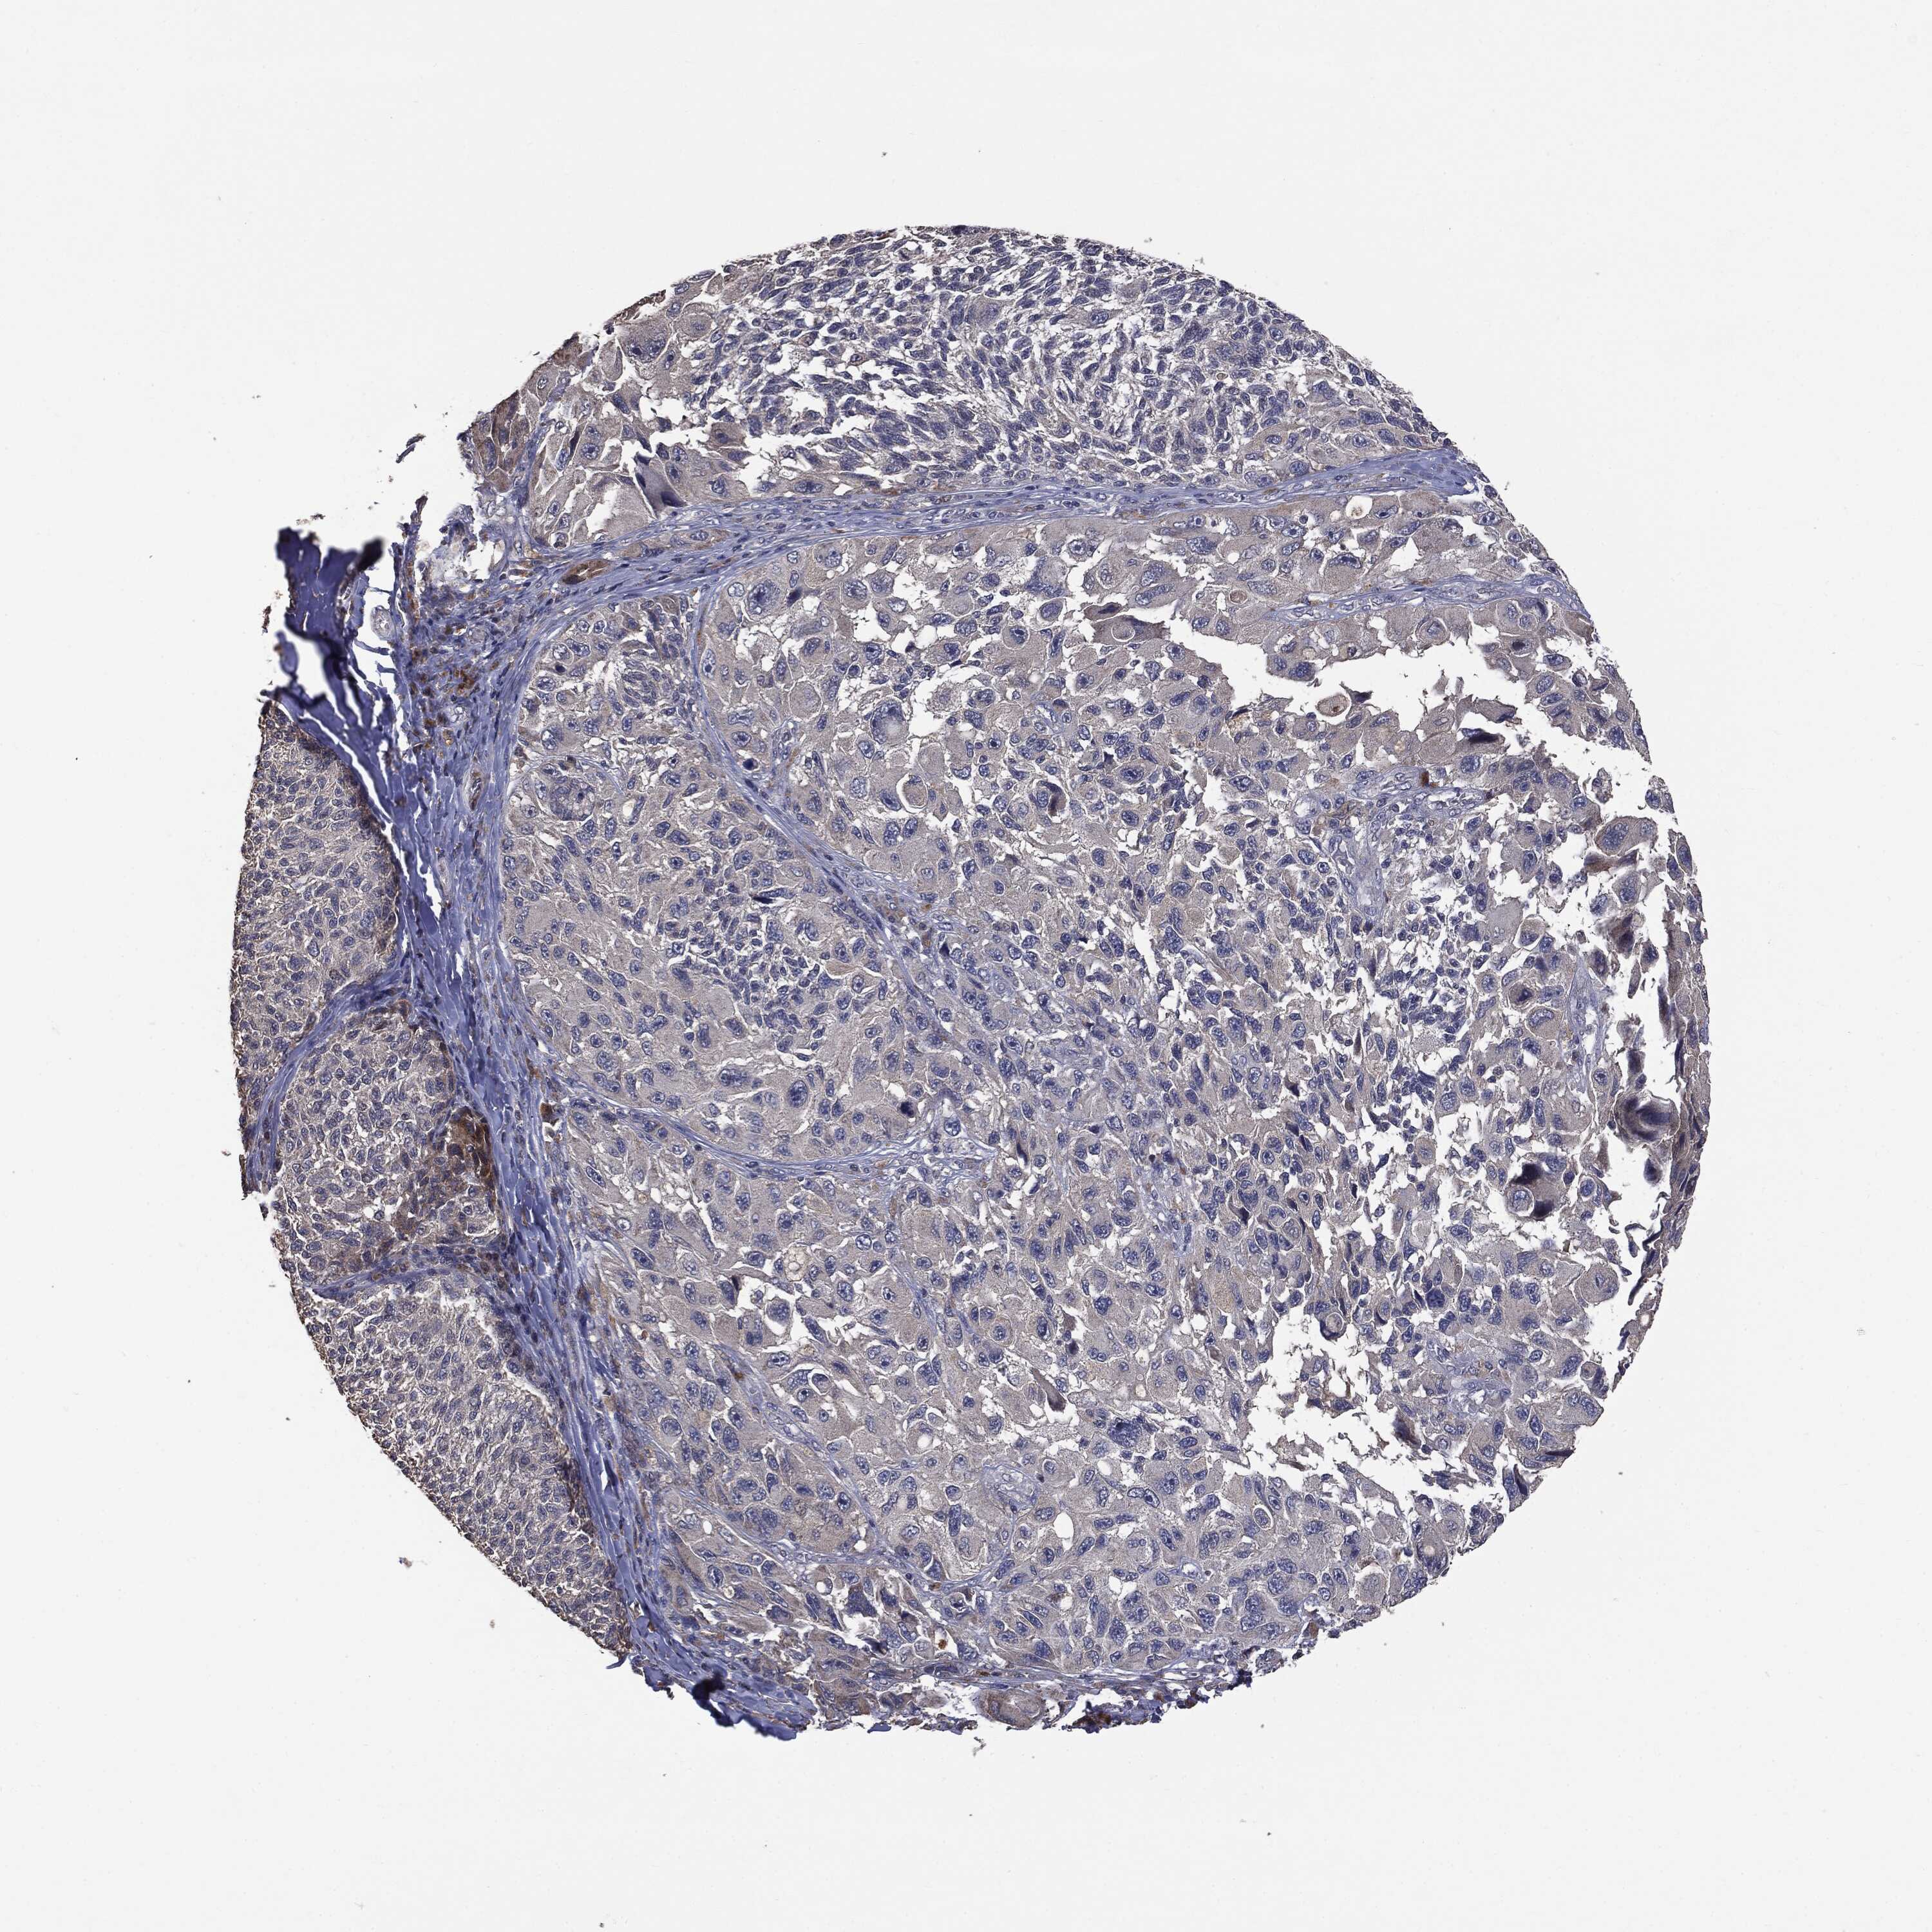

MELANOMA - Protein expressioni

A mouse-over function shows sample information and annotation data. Click on an image to view it in a full screen mode. Samples can be filtered based on level of antibody staining by selecting one or several of the following categories: high, medium, low and not detected. The assay and annotation is described here.

Note that samples used for immunohistochemistry by the Human Protein Atlas do not correspond to samples in the TCGA dataset.

Antibody stainingi

Antibody staining in the annotated cell types in the current human tissue is reported as not detected, low, medium, or high, based on conventional immunohistochemistry profiling in selected tissues. This score is based on the combination of the staining intensity and fraction of stained cells.

Each image is clickable and will lead to virtual microscopy that enables deeper exploration of all samples and also displays staining intensity scores, fraction scores and subcellular localization as well as patient and tissue information for each sample.

CAB069425

CAB080053

CAB080065

CAB080070

CAB080081

CAB080095

CAB080097

Staining

High

Medium

Low

Not detected

Intensity

Strong

Moderate

Weak

Negative

Quantity

>75%

75%-25%

<25%

None

Location

Nuclear

Cytoplasmic/membranous

Cytoplasmic/membranous,nuclear

Malignant melanoma, NOS

Malignant melanoma, Metastatic site